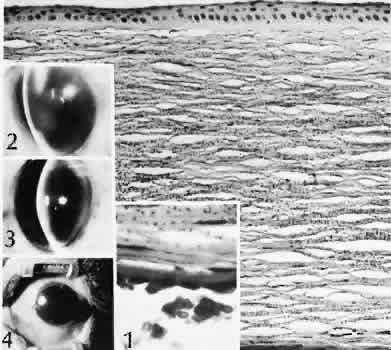

Abrasions are injuries generally involving only the superficial layer (epithelium) of the cornea (Fig. 2). Abrasions are commonly caused by mechanical injuries or anoxia resulting from contact lens overwear. Some or all of the layers of the surface epithelium are lost, but Bowman's membrane remains intact.

Fig. 2. Corneal epithelial cell healing of an abrasion. A. Early in the repair process, epithelial cell layer attenuation is present at the edges of the abrasion (top). The epithelial wound heals by epithelial migration over Bowman's membrane (lower left). Artifactual epithelial breaks have right angle contours (lower right, arrows). (Hematoxylin-eosin stain; × 136.) B. Scanning electron micrograph (SEM) of the leading edge of the corneal epithelium 1 hour after mechanical abrasion. C. SEM of the leading edge of the migrating epithelium. Superficial cells not directly involved in migration may be desquamated. D. Transmission electron micrograph of the leading edge of migrating corneal epithelium 2 hours after mechanical abrasion. Desmosomes are continuous with the wing (W) cell layer overlying a rounded basal cell (BC). Note the loss of hemidesmosomes and the many lateral desmosomes (arrows) between the adjacent basal cells. There are few apical desmosomes between the basal cell on the right and the adjacent wing cell. (B—D: rabbit; × 4000.)

After a delay of approximately 1 hour, uninjured epithelial cells at the margin of the wound loosen their intercellular and basal attachments and migrate en masse toward the injured area.18 The shape of the wound margin and the biochemical characteristics of the exposed tissue influence the direction and extent of the migration.19 If the entire corneal epithelium is abraded, migrating epithelial cells derived from the limbal stem cells are able to cover the defect completely within 48 to 72 hours. The epithelium will be much thinner than normal until mitotic division reestablishes normal thickness. Re-formation of epithelial basement membrane may not be detectable for as long as 6 weeks after injury.20 Clinically, the healed wound is transparent.

Small defects of Bowman's membrane (Fig. 3) do not heal by fibrous proliferation of the stroma. The defect is filled by proliferating epithelial cells (epithelial facet formation) that reestablish the surface continuity of the cornea. The facet may be seen clinically as a focal, well-demarcated, superficial corneal opacity. A corneal foreign body causes this lesion most often.

Fig. 3. Epithelial facet. The superficial defect between the cut edges of Bowman's membrane (arrows) is filled with epithelial cells in such a manner as to reestablish the original surface contour of the cornea. Bowman's membrane will not regenerate in this area. Because of the limited extent of the injury, the underlying collagenous tissue does not participate in the wound healing process. (Wilder reticulum stain; × 145.)

Penetrating corneal injuries involving at least one third of the stroma (Fig. 4) are covered initially by proliferating surface epithelium that may extend for a considerable distance into the stroma. The extent of corneal epithelial migration is controlled at least in part by contact inhibition of migration once contact with healthy corneal endothelial cells is established.21 Bowman's membrane has elastic properties that tend to pull the anterior margins of the wound apart. Exposure of the relatively dehydrated corneal stroma to tears and blood will cause swelling of the corneal stroma. This swelling of the stroma tends to close the wound. As the stroma heals, new collagen is produced by keratocytes or transformed monocytes. Epithelial cells will regress toward the surface. The repair collagen is different from the native collagen in size and in orientation. The healed wound is densely opaque and obvious clinically, but it may be detected histologically only by the break in Bowman's membrane.

Fig. 4. Deep stromal defect. In the area of the defect (right) the epithelium is hyperplastic, Bowman's membrane is absent, and the corneal stroma is thinned. A stromal scar is characterized by and increased number and haphazard arrangement of keratocytes. (Hematoxylin-eosin stain; × 100.)